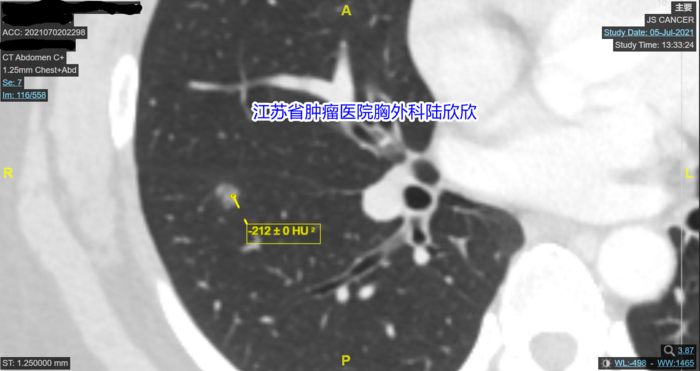

最大CT值-192的图我一时找不到了。我下面有两张图。最大CT值是-197和-212,和-192已结很接近了。

我再观察,发现结节的外形有点不规则,这也是肺癌的一个表现。我测量了磨玻璃结节内部多点的CT值,我说:“你的结节最大CT值是-192,磨玻璃结节周围有环状强化,内部有点状实性成分。所以这个混合磨玻璃结节不可能是原位癌,磨玻璃结节如果是原位癌的话,密度很均匀,一般没有实性成分,形状接近于球形。你的磨玻璃结节密度不均匀,而且有点状实性成分,局部形状不规则,所以可以排除原位癌。那么有没”有可能是微小浸润性腺癌呢?最大CT值我测给你看,大约-192。磨玻璃结节中微小浸润性腺癌的CT值要高一些,一般在-560到-460之间。磨玻璃结节中浸润性腺癌的CT值要更高一些,一般在-460以上,平均值-260左右你的磨玻璃结节最大CT值我刚才测量了,大约-192,CT室医生测量平均CT值-378,所以这个磨玻璃结节应该超过了微小浸润性腺癌的阶段,现在估计已经到了浸润性腺癌的阶段。所以,我的结论和省人民医院和我们医院影像科的看法不一样,他们都认为很可能是微小浸润性腺癌,我认为最可能的诊断是浸润性腺癌。当然也不能排除炎性病变,不过可能性很小。另外,这个结节贴近肺裂胸膜,如果是恶性的磨玻璃结节,比较危险,将来有侵犯胸膜的危险。最好手术切除。手术可以基本上治愈。